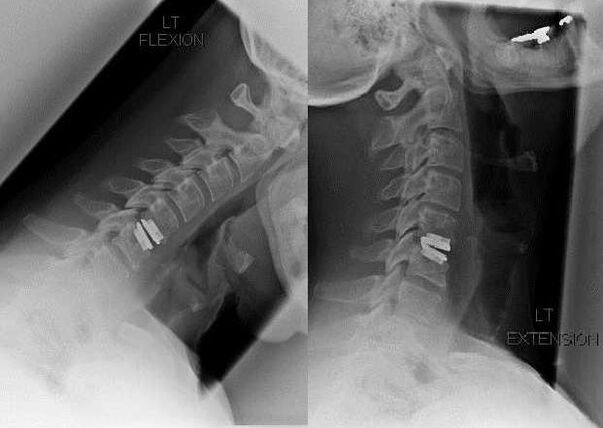

Surgery

Indications for surgical intervention include the ineffectiveness of conservative treatment, as well as complications of cervical osteochondrosis, for example, discogenic myelopathy, vertebral artery syndrome and radicular syndrome.To decompress the spinal cord, blood vessels and spinal roots, the following operations are performed:

During the surgical procedure, bone fragments and ligaments can be excised and the intervertebral discs can be completely or partially removed.For small hernial protrusions, laser vaporization of the disc nucleus is often performed.

After excision of spinal structures, stabilization of spinal motion segments is often necessary by spinal fusion or by placement of bone and skin autografts.